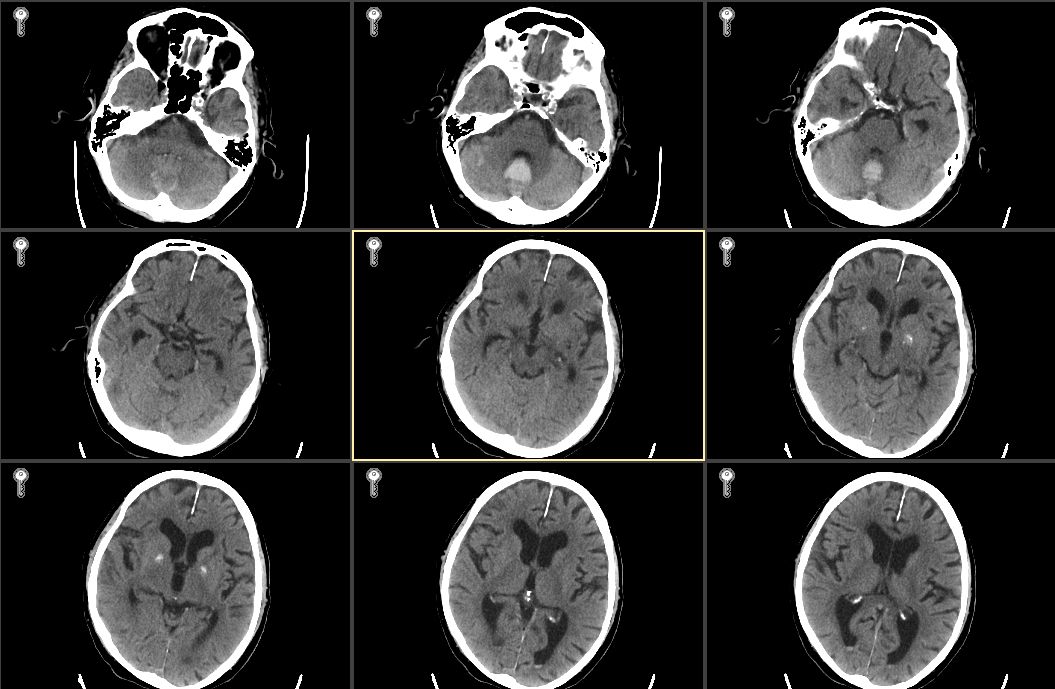

1 资料与方法病例1,男性,87岁,因“洗澡后突发头痛,呕吐半天”急诊入院。既往史有高血压病史数十年,血压控制良好;冠心病史,2007年接受“冠脉搭桥术”,长期服用拜阿司匹林325 mg 1次/d,辛伐他汀80 mg 1次/晚。入院查体:格拉斯哥昏迷评分法(Glasgow Coma Scale,GCS)14分,双瞳等大等圆,光敏,四肢肌力正常,双侧病理征阴性。入院头颅CT(图 1)示小脑蚓部血肿,量约7 mL,四脑室和环池清晰;双侧额顶叶,脑室旁多发缺血腔隙灶,脑萎缩。CTA提示未见明显异常。

| 图 1 2007年5月11日患者入院第1天头颅CT |